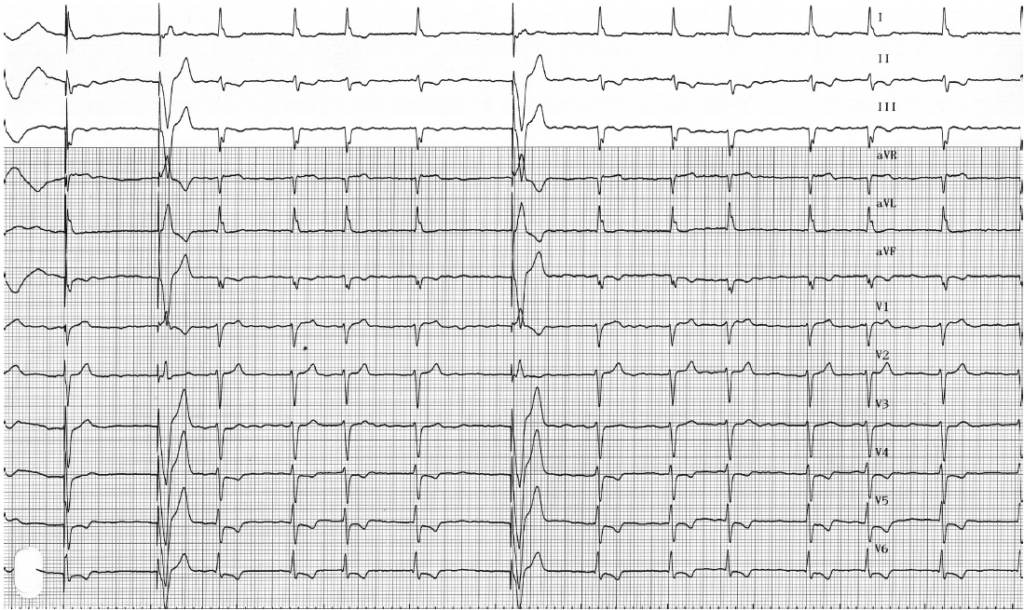

L’EGM montre le ralentissement et la régularisation de la fréquence de stimulation à la suite de la programmation de l’algorithme de commutation de mode;

Ces tracés montrent le fonctionnement normal d’un stimulateur double chambre lors d’un épisode de fibrillation auriculaire; la programmation de la commutation de mode permet un retour à une fréquence cardiaque plus physiologique que sur les tracés précédents. Pour éviter une chute brutale de la fréquence ventriculaire, le retour à la fréquence de base ou à la fréquence asservie est progressif.

L’EGM confirme le diagnostic de FA conduite avec quelques cycles stimulés quand la fréquence atteint la fréquence minimale programmée;

Le ralentissement de la fréquence de stimulation permet la réapparition du rythme spontané; l’allongement des diastoles ventriculaires permet de mieux visualiser la détection d’une arythmie atriale rapide et désorganisée; la stimulation ventriculaire ne survient plus que sur les quelques diastoles longues (FA lente);